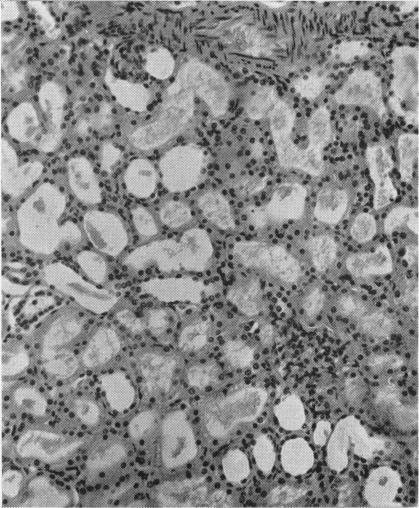

CROME L

Arch Dis Child. 1962 Aug;37(194):415-21. doi: 10.1136/adc.37.194.415.